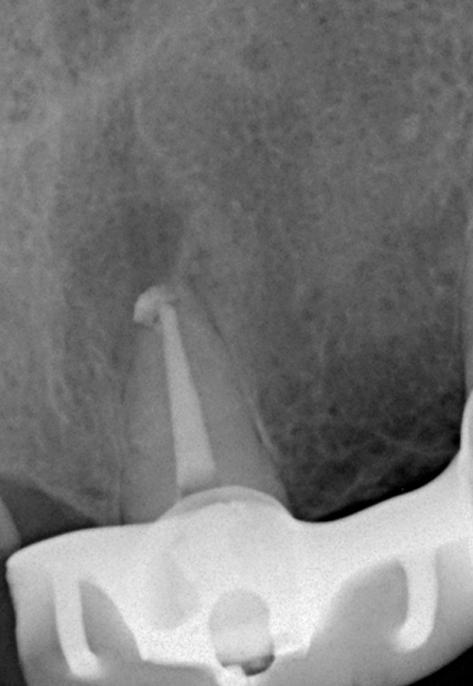

Выявлена болезненность при перкуссии и пальпации в области 21 зуба. Зуб не реагирует на термические раздражители. Результаты пародонтологического обследования в пределах нормы, рентгенологическое обследование выявило радиолюцентную зону в области верхушки корня (снимки 1, 2).

Диагноз: Острый апикальный периодонтит.